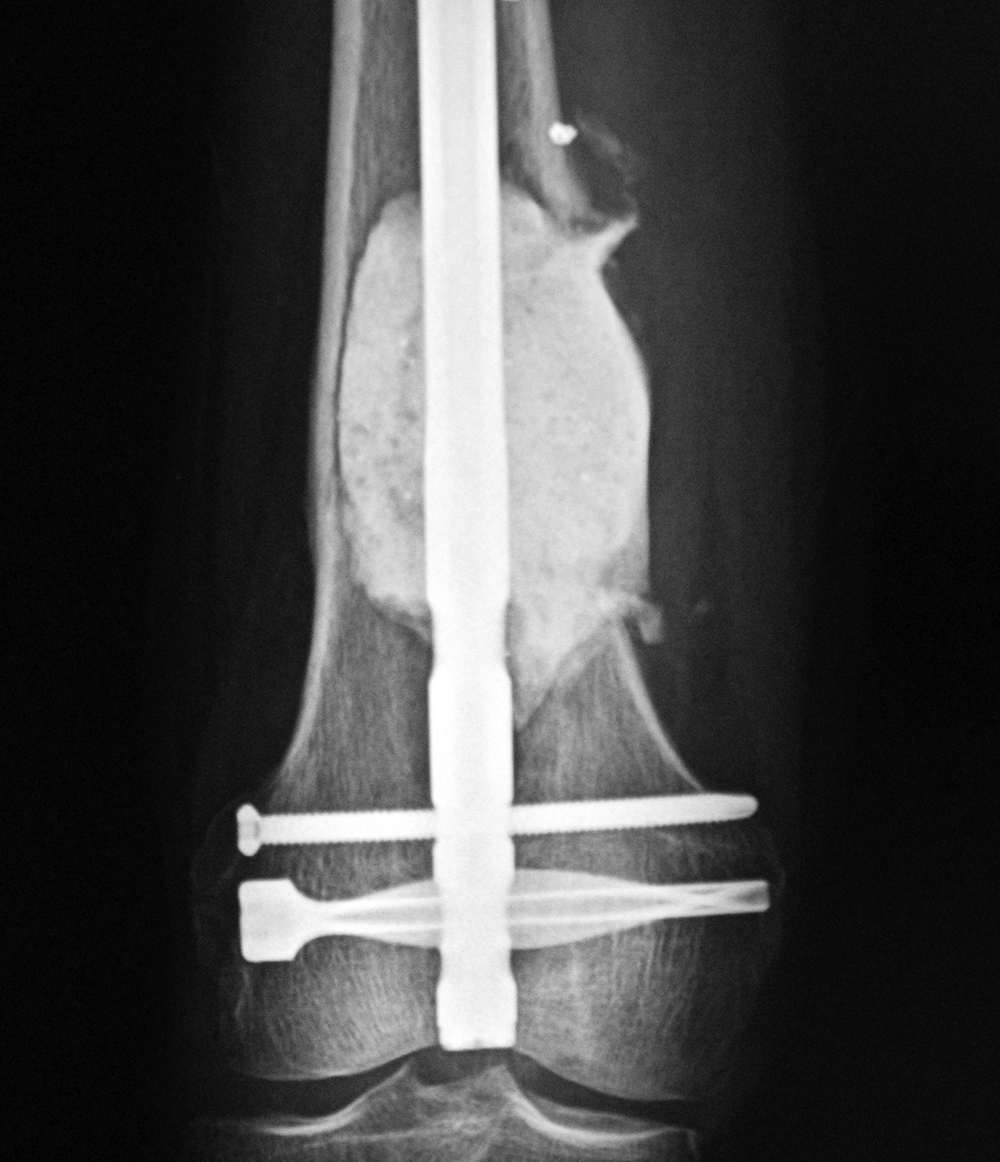

43 year-old man with comminuted right tibia and fibula fractures as well as extensive bone loss and soft tissue injury. A tibial intramedullary nail with proximal and distal locking screws is present as well as multiple rounded bony allografts. There are also large skin staples.